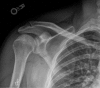

Over the past few decades, there has been increased awareness of pectoralis major muscle injuries necessitating further evaluation of management options and, in particular, surgical repair. Injury typically occurs when an eccentric load is applied to the muscle, such as with bench pressing, and failure usually occurs through the tendon. Although nonoperative management is sometimes appropriate, given the injury's propensity for young, active male patients, surgical intervention is often warranted. Because the injury typically occurs at the muscle-tendon interface, surgery focuses on repair of the avulsed tendon into its anatomic attachment site. We describe the use of a unicortical suture button to repair the ruptured tendon. This technique achieves the goals of strong fixation and anatomic repair of the tendon back into its native footprint.